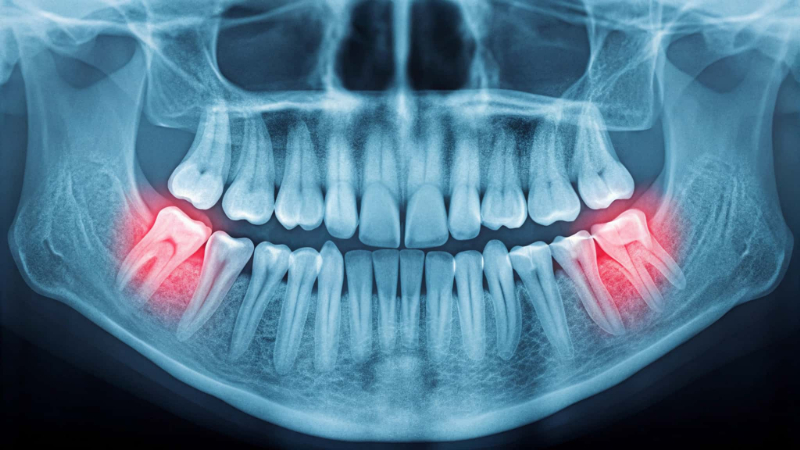

親知らずが横向きや斜めに生えることも多くあります。これは顎のスペースが足りないために起こる代表的なケースです。歯ぐきの中に埋まったまま、見えない状態で横向きになっていることもあります。

このような生え方をしていると、隣接する歯を押し続けて、歯並びが乱れることがあります。また、親知らずの周囲に汚れが溜まりやすく、虫歯や炎症を起こす原因にもなりやすいのが特徴です。

レントゲンを撮ることで、親知らずの状態を確認できます。これによってトラブルを早めに見つけることができれば、将来的にトラブルが起こるリスクを大きく減らすことができます。